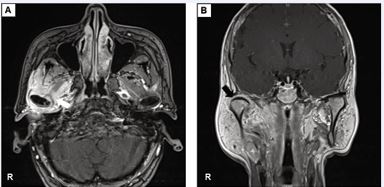

An erythrocyte sedimentation rate of 54 mm/h was detected, with normal results for the complete blood count and C-reactive protein. A computed tomography (CT) scan showed low-density shadows in the right tympanic cavity and mastoid process, bony erosion in the anteroinferior wall of EAC leading into the mandibular fossa, and massive low-density shadows around the condyle [Figure 1]. Magnetic resonance imaging (MRI) with contrast exhibited enhancement around the right TMJ and adjacent muscles [Figure 2].

Figure 2 Magnetic resonance imaging (MRI) with contrast of the maxillofacial region. (A) The axial view showed peripheral enhancement signals of the right temporomandibular joint and surrounding muscles (white arrow). (B) The coronal view exhibited swollen inflammatory tissue around the mandibular condyle (black arrow).